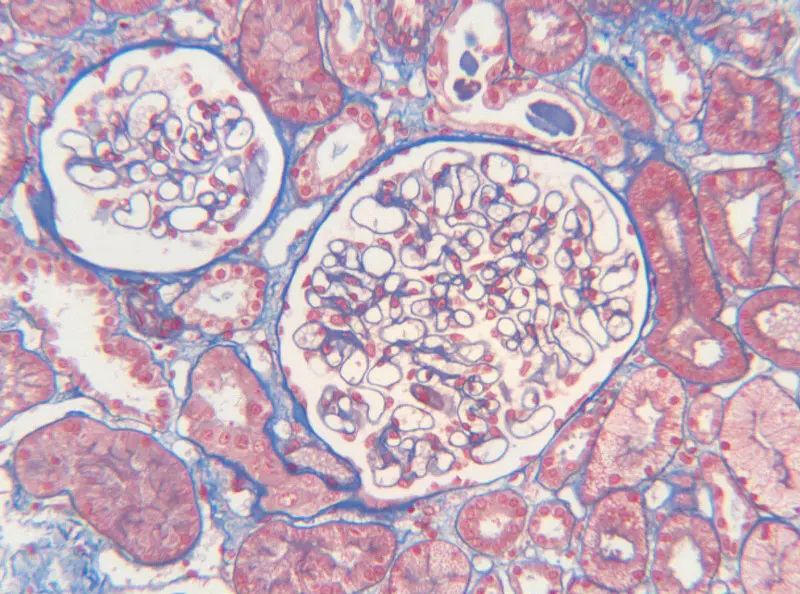

MASSON染色原理及其陽性意義是醫(yī)學和生物學領域中的關鍵概念,特別是在對組織結構和成分進行分析時。MASSON染色是一種特殊的組織染色方法,主要依賴于不同離子染料的分子大小和組織滲透性的差異,從而實現(xiàn)對不同組織成分的區(qū)分和著色。

首先,讓我們深入探討MASSON染色的原理。MASSON染色的原理與陰離子染料分子的大小和組織的滲透性密切相關。染料的分子量決定了其穿透組織的能力:小分子量的染料更容易穿透結構致密、滲透性較低的組織,而大分子量的染料則更傾向于進入結構疏松、滲透性較高的組織。在MASSON染色中,由于肌纖維間隙較小,而膠原纖維間隙較大,因此小分子量的麗春紅染料更容易滲透進入肌纖維并使其呈現(xiàn)紅色,而大分子量的苯胺藍染料則主要進入膠原纖維并使其呈現(xiàn)藍色或綠色。

MASSON染色的陽性意義在于,它能夠幫助研究人員區(qū)分膠原纖維和肌纖維,從而觀察病變組織中纖維結締組織的增生和分布。當MASSON染色結果呈現(xiàn)陽性時,通常意味著局部組織中存在膠原纖維的增生。這種增生可能是由于局部皮膚出現(xiàn)炎癥或組織增生等病理 過程所導致的。因此,MASSON染色的陽性結果可以作為判斷組織纖維化程度的一個重要指標。